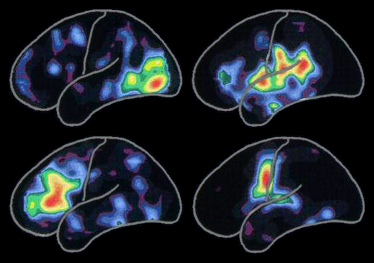

Der Positronen-Emissions-Tomographie (PET)-Scan links veranschaulicht die üblichen Muster der Gehirnaktivität, die mit folgenden Aktivitäten verbunden sind:

Die Gehirnaktivität ist in den roten Bereichen am stärksten. Das Nachlassen der Gehirnaktivität wird anhand der anderen Regenbogenfarben, von gelb bis blau-violett, dargestellt.

Spezifische Aktivitätsmuster ändern sich im Lauf unseres Lebens, etwa wenn wir neue Menschen kennenlernen, neue Erfahrungen machen und neue Fähigkeiten erwerben. Die Muster ändern sich auch, wenn durch die Alzheimer-Krankheit oder ähnliche Krankheiten Nervenzellen und ihre Verbindung untereinander gestört werden.